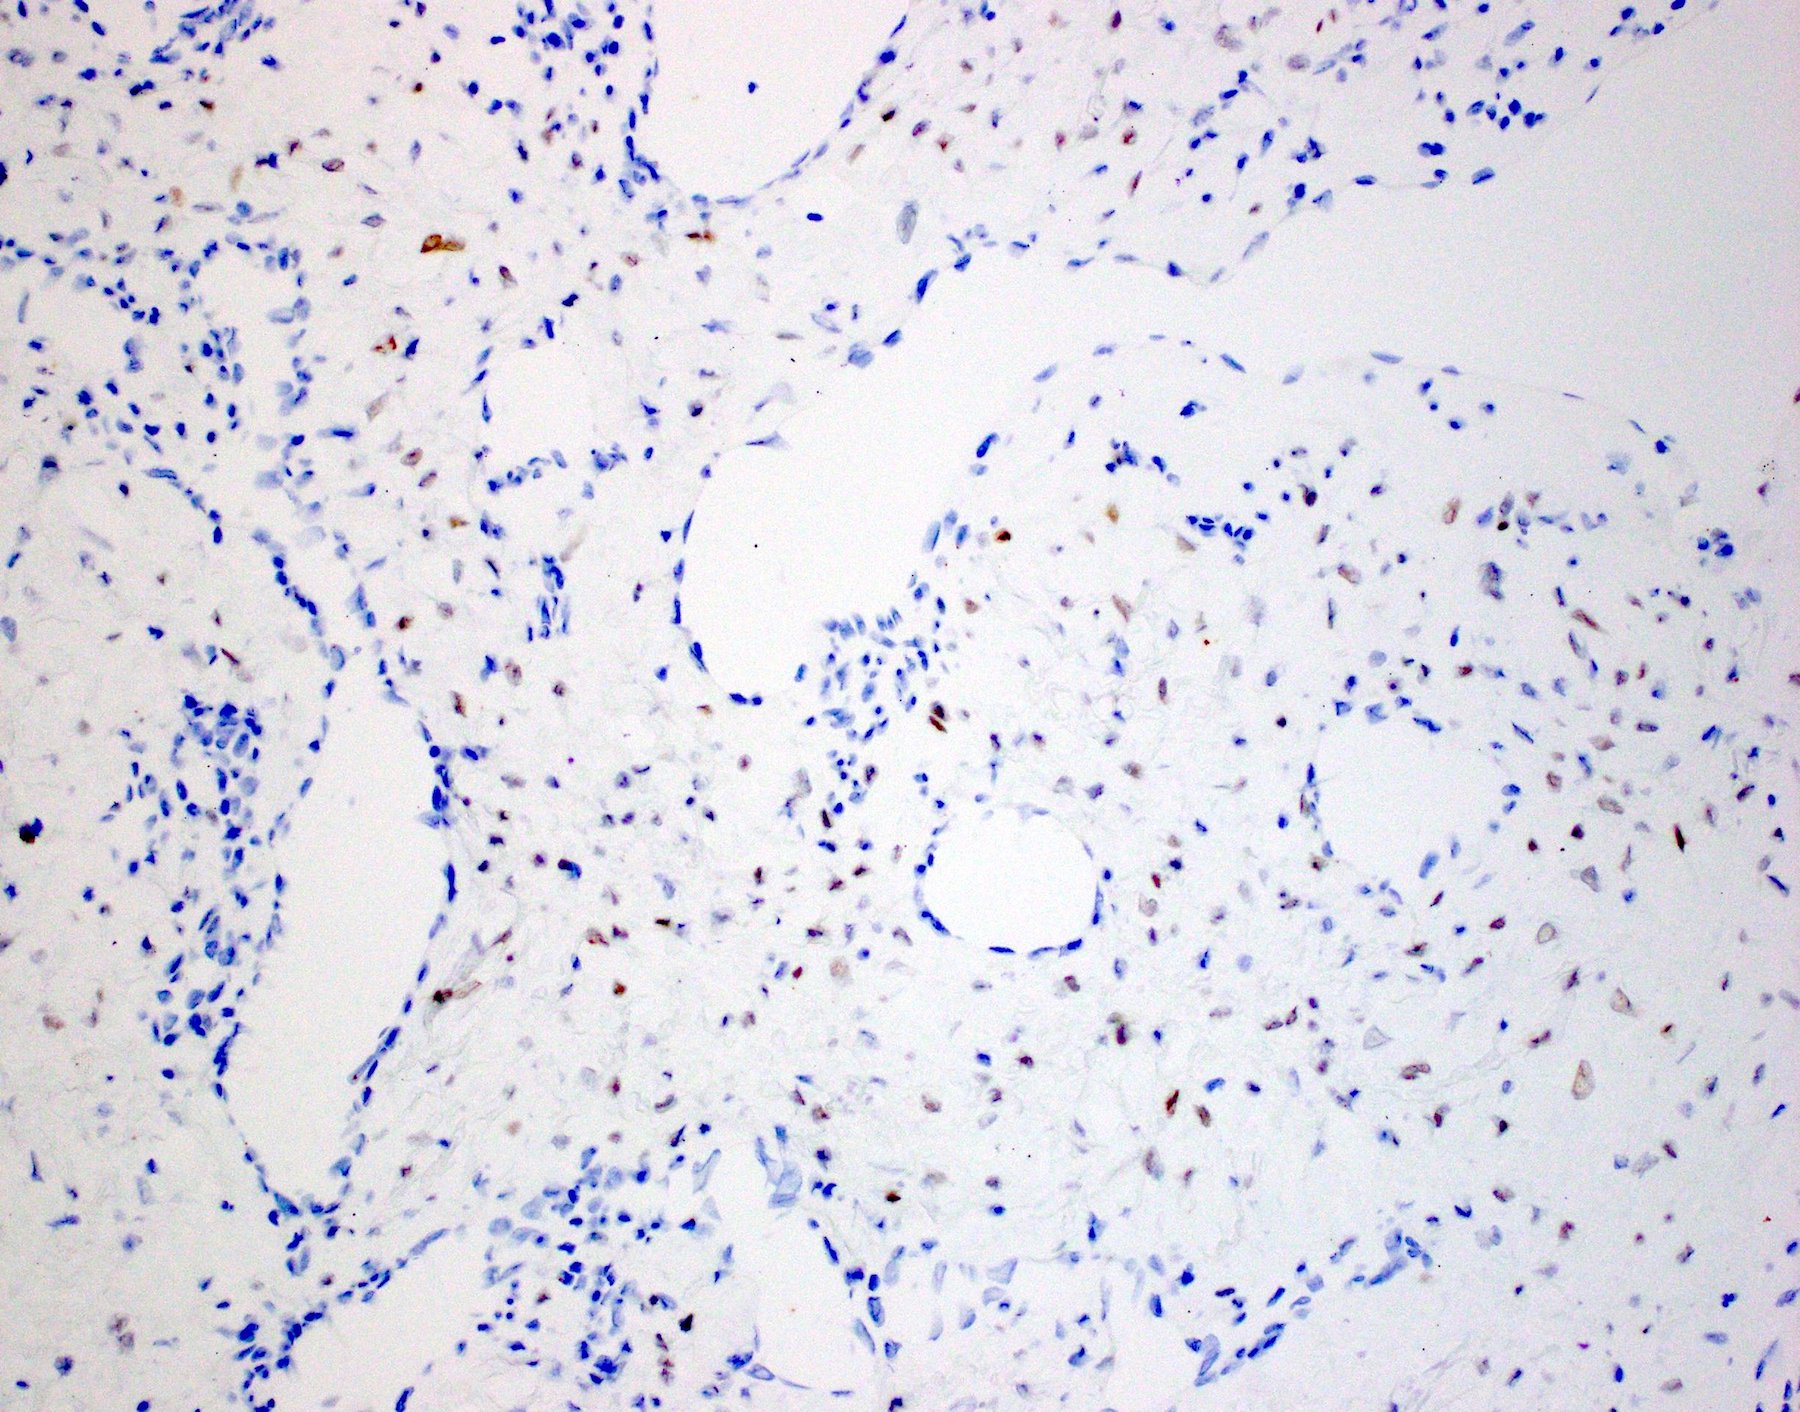

Positive stains

- AR is positive in stroma cells in 40 - 75% cases; the expression may be focal and weak (Acta Otolaryngol 2015;135:51, Am J Clin Pathol 2006;125:832, Mod Pathol 1998;11:1122)

- Beta catenin: nuclear staining in stromal cells (fibroblasts) in 70 - 90% of cases, membranous / cytoplasmic staining in endothelial cells (J Laryngol Otol 2016;130:907)

Microscopic (histologic) images

Contributed by Bin Xu, M.D., Ph.D.

Contributed by Kelly Magliocca, D.D.S., M.P.H.